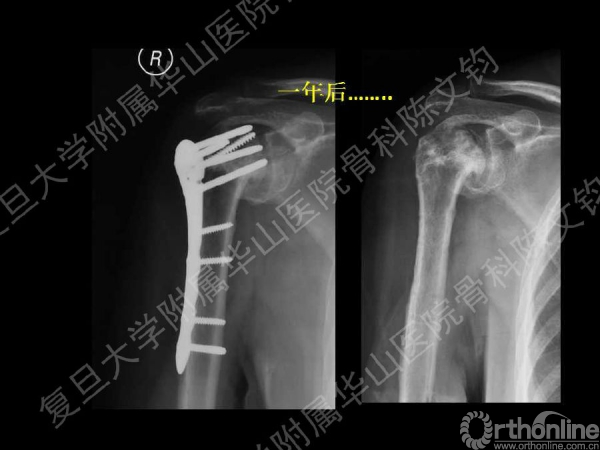

一年后复查:右肱骨头吸收坏死

注意:只要可以满足功能,没有疼痛的问题,不要轻易做反肩关节置换。如果要行反肩置换一定要全面衡量,做好充分准备。